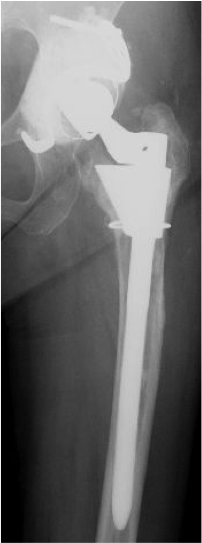

人工関節置換術(THA)

特に関節が強く破壊された状態を「末期」といい、通常は人工関節しか方法はありません。人工股関節に置換することによって、関節の痛みや歩行障害などが改善すると思われます。手術後は、リハビリテーションプログラムにそってリハビリを行い、通常の手術では術翌日から歩行を開始し、入院期間は2週間の予定です。

手術後の合併症として感染、脱臼、血栓症(下肢静脈血栓症、肺血栓症)、人工股関節のゆるみなどがありますが、種々の対策を講じて、その発生の予防に努力しています。